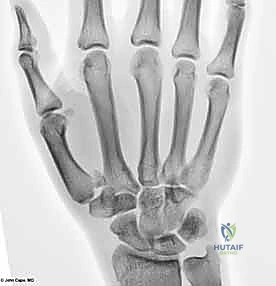

يتكون هذا المفصل من التقاء قاعدة عظم المشط الأول للإبهام (First Metacarpal Bone) مع العظم المربعي (Trapezium) الموجود في صف عظام الرسغ. يُصنف هذا المفصل من الناحية التشريحية على أنه "مفصل سرجي حقيقي" (Saddle Joint). هذا يعني أن الأسطح المفصلية لكلا العظمين تتخذ شكلاً مقعراً في اتجاه ومحدباً في الاتجاه الآخر، مما يسمح لها بالتشابك التام.

2. التصوير بالأشعة السينية (X-rays)

هي الأداة التشخيصية الأولى والأهم. يتم إجراء صور أشعة بزوايا محددة جداً:

* المنظور الأمامي الخلفي (AP View).

* المنظور الجانبي الحقيقي (True Lateral View): وهو ضروري جداً لتقييم مدى الخلع أو الانزياح في المفصل.

* منظور روبرت (Robert's View): وضعية خاصة للأشعة السينية تظهر مفصل الإبهام الرسغي السنعي بوضوح تام وتكشف عن أدق التفاصيل في كسور بينيت ورولاندو.